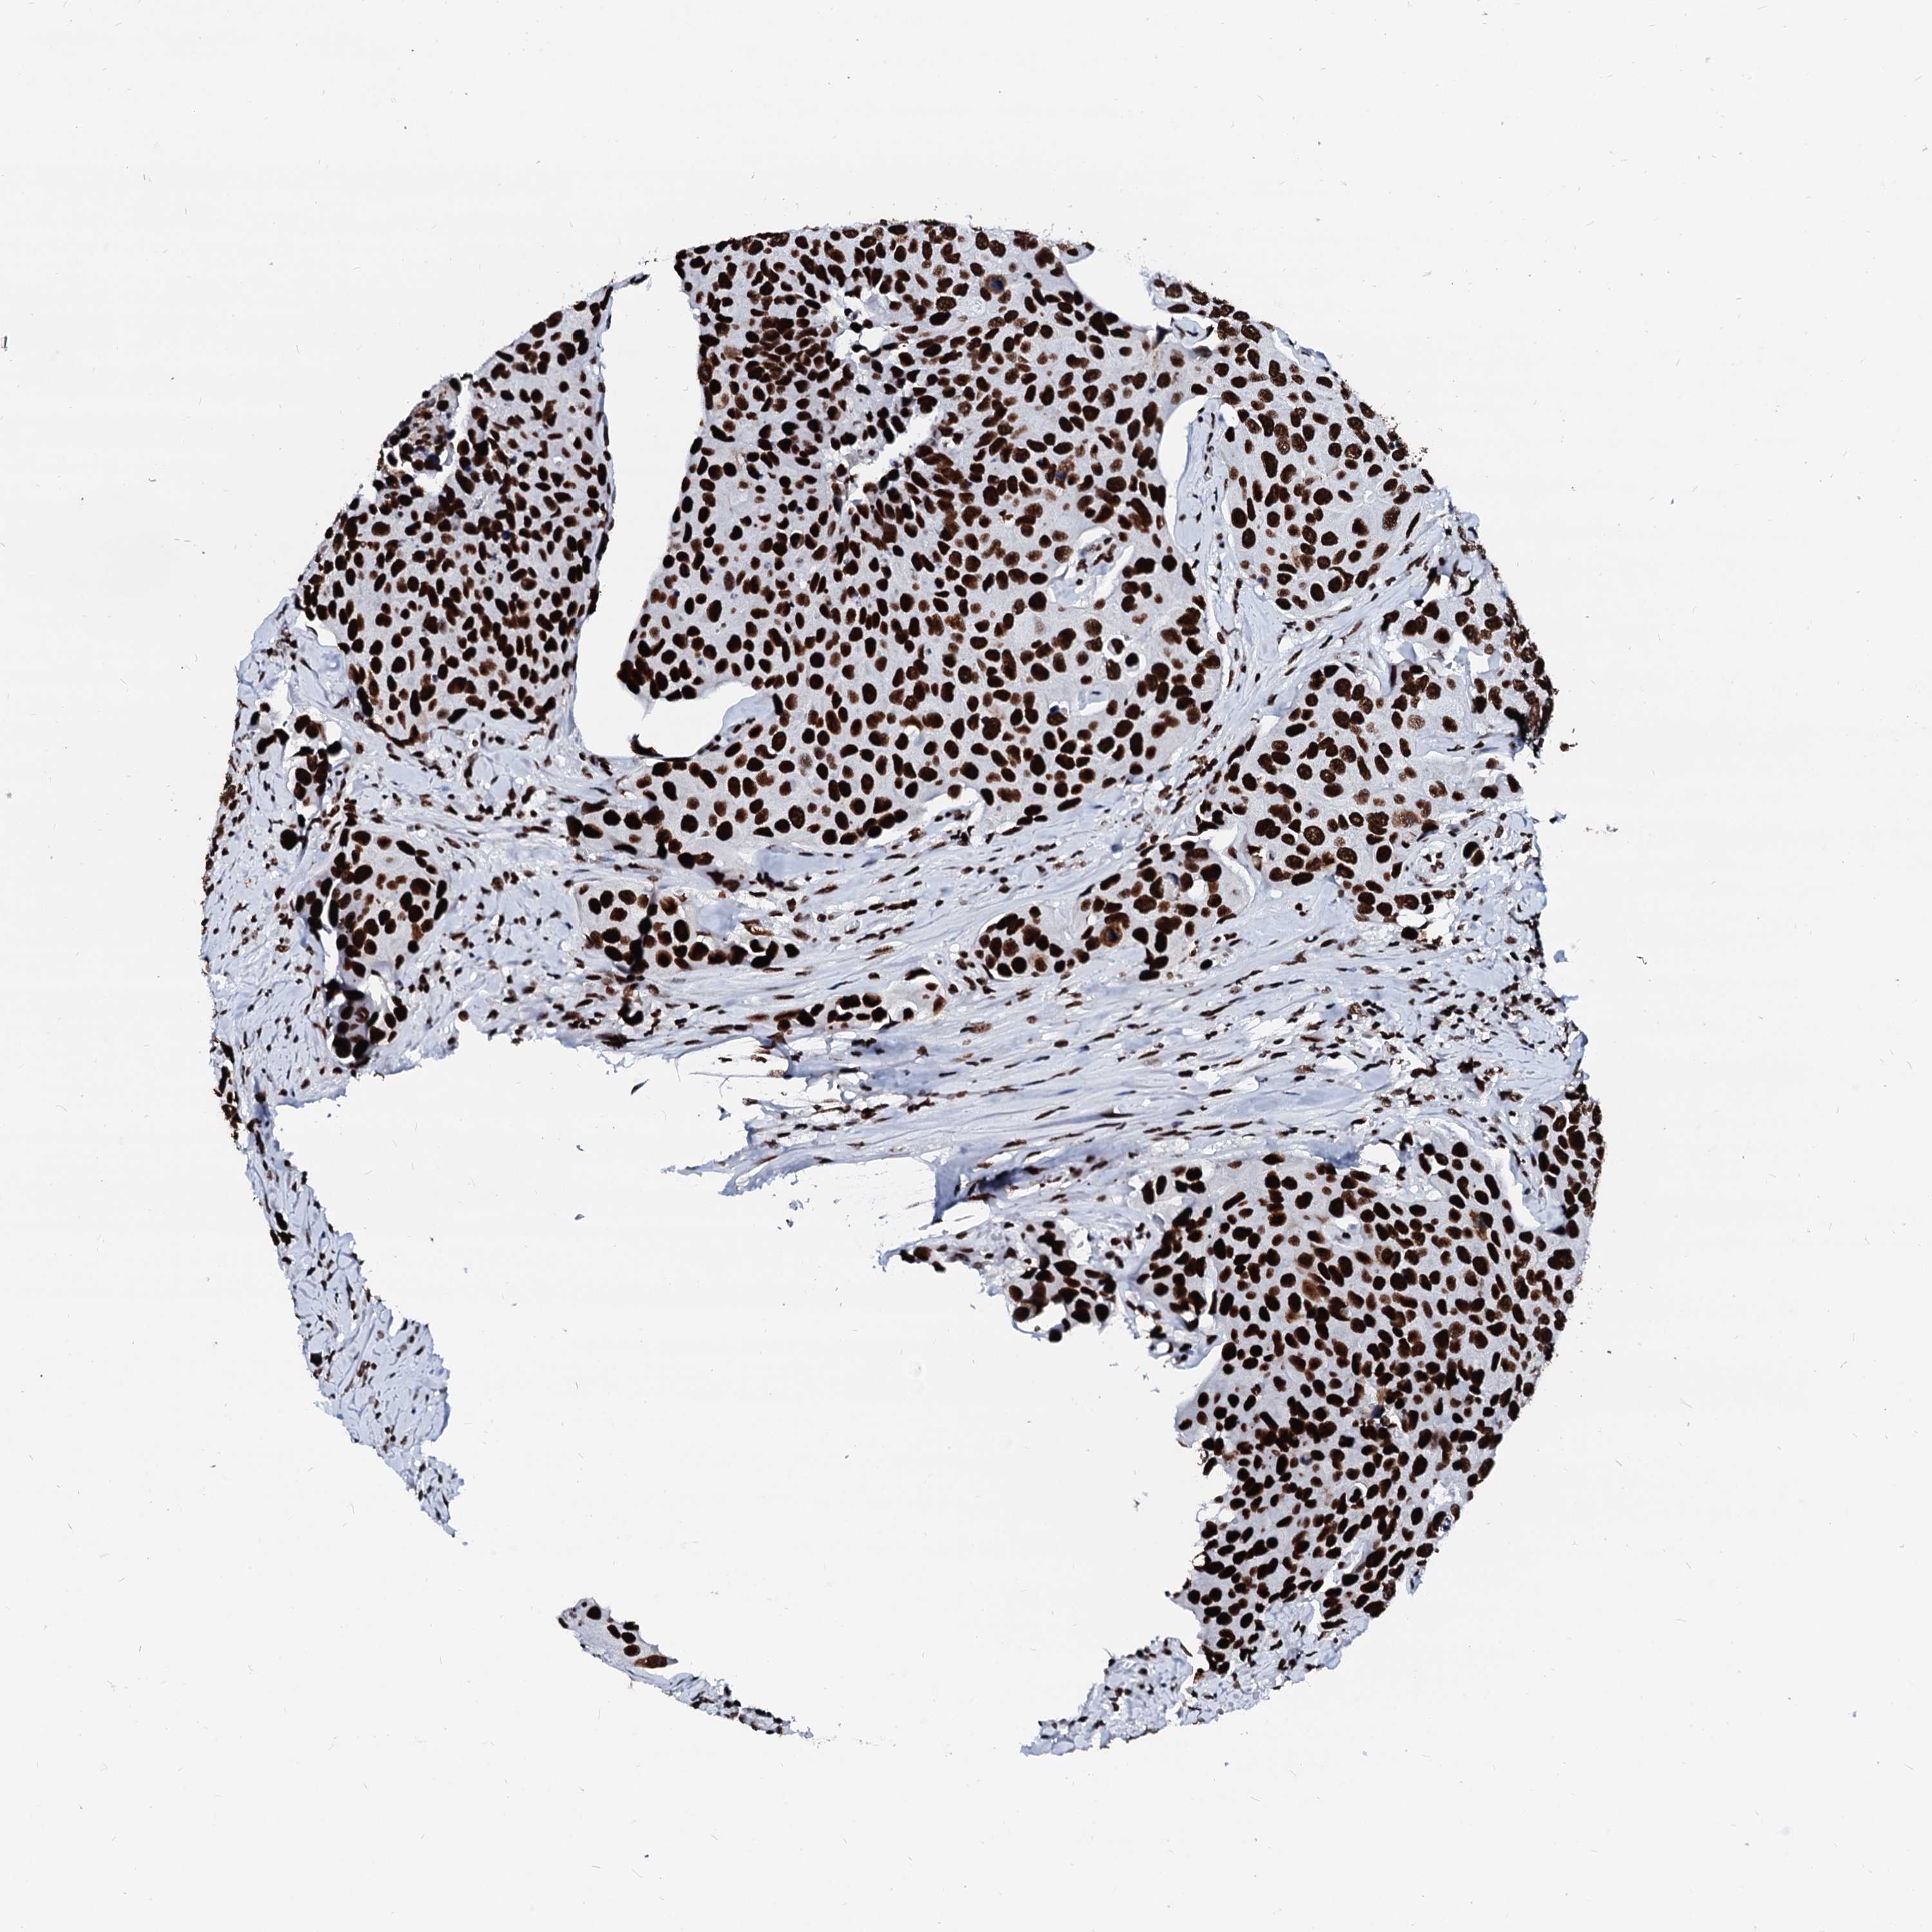

UROTHELIAL CANCER - Protein expressioni

A mouse-over function shows sample information and annotation data. Click on an image to view it in a full screen mode. Samples can be filtered based on level of antibody staining by selecting one or several of the following categories: high, medium, low and not detected. The assay and annotation is described here.

Antibody stainingi

Antibody staining in the annotated cell types in the current human tissue is reported as not detected, low, medium, or high, based on conventional immunohistochemistry profiling in selected tissues. This score is based on the combination of the staining intensity and fraction of stained cells.

Each image is clickable and will lead to virtual microscopy that enables deeper exploration of all samples and also displays staining intensity scores, fraction scores and subcellular localization as well as patient and tissue information for each sample.

Antibody HPA040971

Antibody HPA043614

Staining

High

Medium

Low

Not detected

Intensity

Strong

Moderate

Weak

Negative

Quantity

>75%

75%-25%

<25%

None

Location

Nuclear

Cytoplasmic/membranous

Cytoplasmic/membranous,nuclear

Urothelial carcinoma, High grade